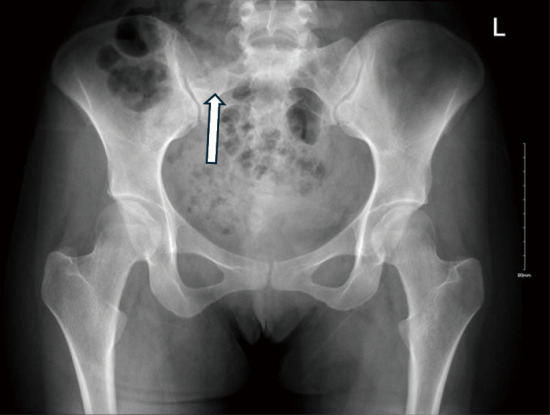

Case description: A 23-year-old female known case of ovarian cyst presented with a two-year history of low back pain and constitutional symptoms. Pelvic magnetic resonance imaging (MRI) with contrast showed a well-defined lesion with intermediate to high signals located at the right wing of the upper sacrum, at the level of S1-S2. The patient underwent a combined ultrasound and computed tomography-guided biopsy under local anesthesia and the immunochemical profile was positive for CD99 and S100 biomarkers. The patient underwent a two-stage procedure for a wide marginal tumor resection. Stage 1 was performed with an anterior approach; identification of the tumor margins was done followed by designing the cuts of the sacrum to achieve wide margins around the tumor. Stage 2 was performed with a posterior approach exposing L3 vertebrae down to the sacrum. Utilizing O-Arm Navigation for posterior margin allocation in addition to instrumentation. After 12 months post-operation, follow up revealed no evidence of recurrence.